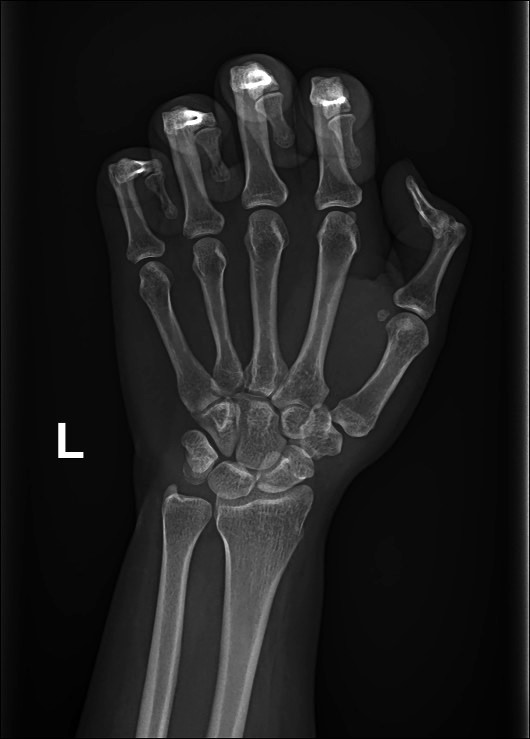

AP